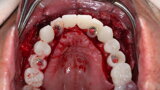

Compromised maxillary dentition treated with Straumann Pro Arch and a digital workflow